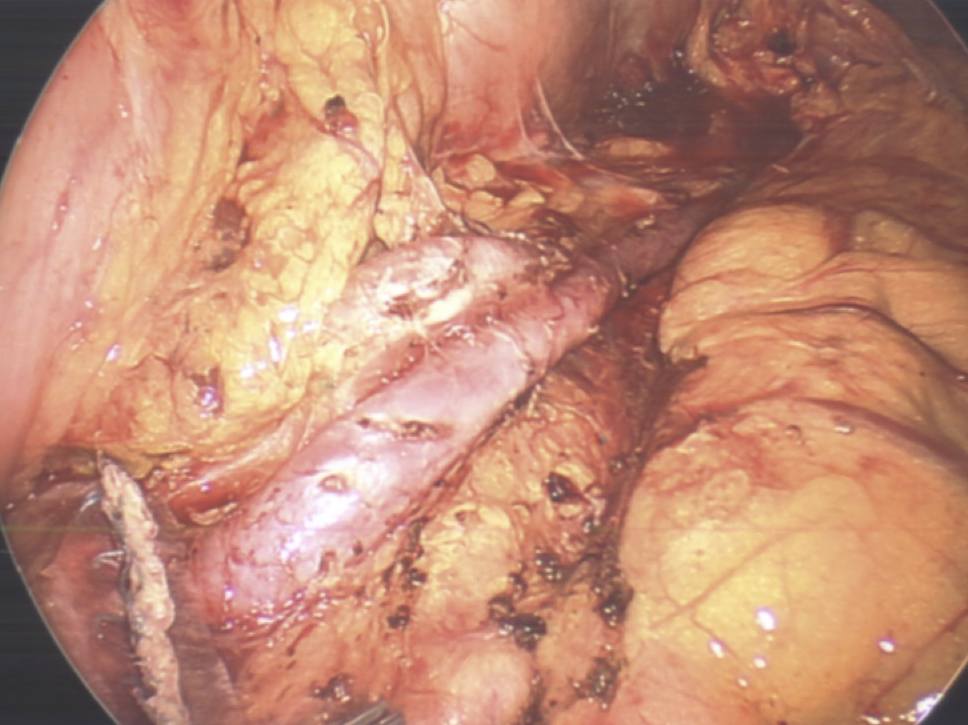

With many years experience as a liver transplant surgeon, Dr. de la Torre was the first to perform a major liver resection laparoscopically in the state of New Jersey, and has been performing laparoscopic liver surgery since 2007. Dr. de la Torre has 25 years of experience in surgery of the liver, pancreas, bile ducts, management of cirrhosis, portal hypertension, and liver cancer. Dr. De la Torre specializes in tissue sparing laparoscopic liver surgery in patients with cirrhosis, allowing the possibility of avoiding liver transplant for tumors located in the liver that were once deemed not feasible to remove. Dr. de la Torre published "A Sling Technique For Laparoscopic Resection of Segment Seven of the Liver" in the Journal of the Society of Laparoendoscopic Surgery 2018 Apr-Jun; 22(2) and most recently "Sling Technique for Laparoscopic Liver Mobilization" Journal of the Society of Laparoscopic and Robotic Surgeons 2024 Apr-Jun;28(2). While most other surgeons in New Jersey start laparoscopically and eventually open, 95% of our patients start laparoscopically and end laparoscopically without compromise in surgical quality or safety.

In addition to laparoscopic liver surgery, Dr de la Torre specializes in laparoscopic pancreas surgery, performing the Whipple Procedure through a 3-4 inch incision. The pancreas leak rate has been 0%. Patients have less pain, shorter hospital stay (4-7 days) and even a lower hospital bill.